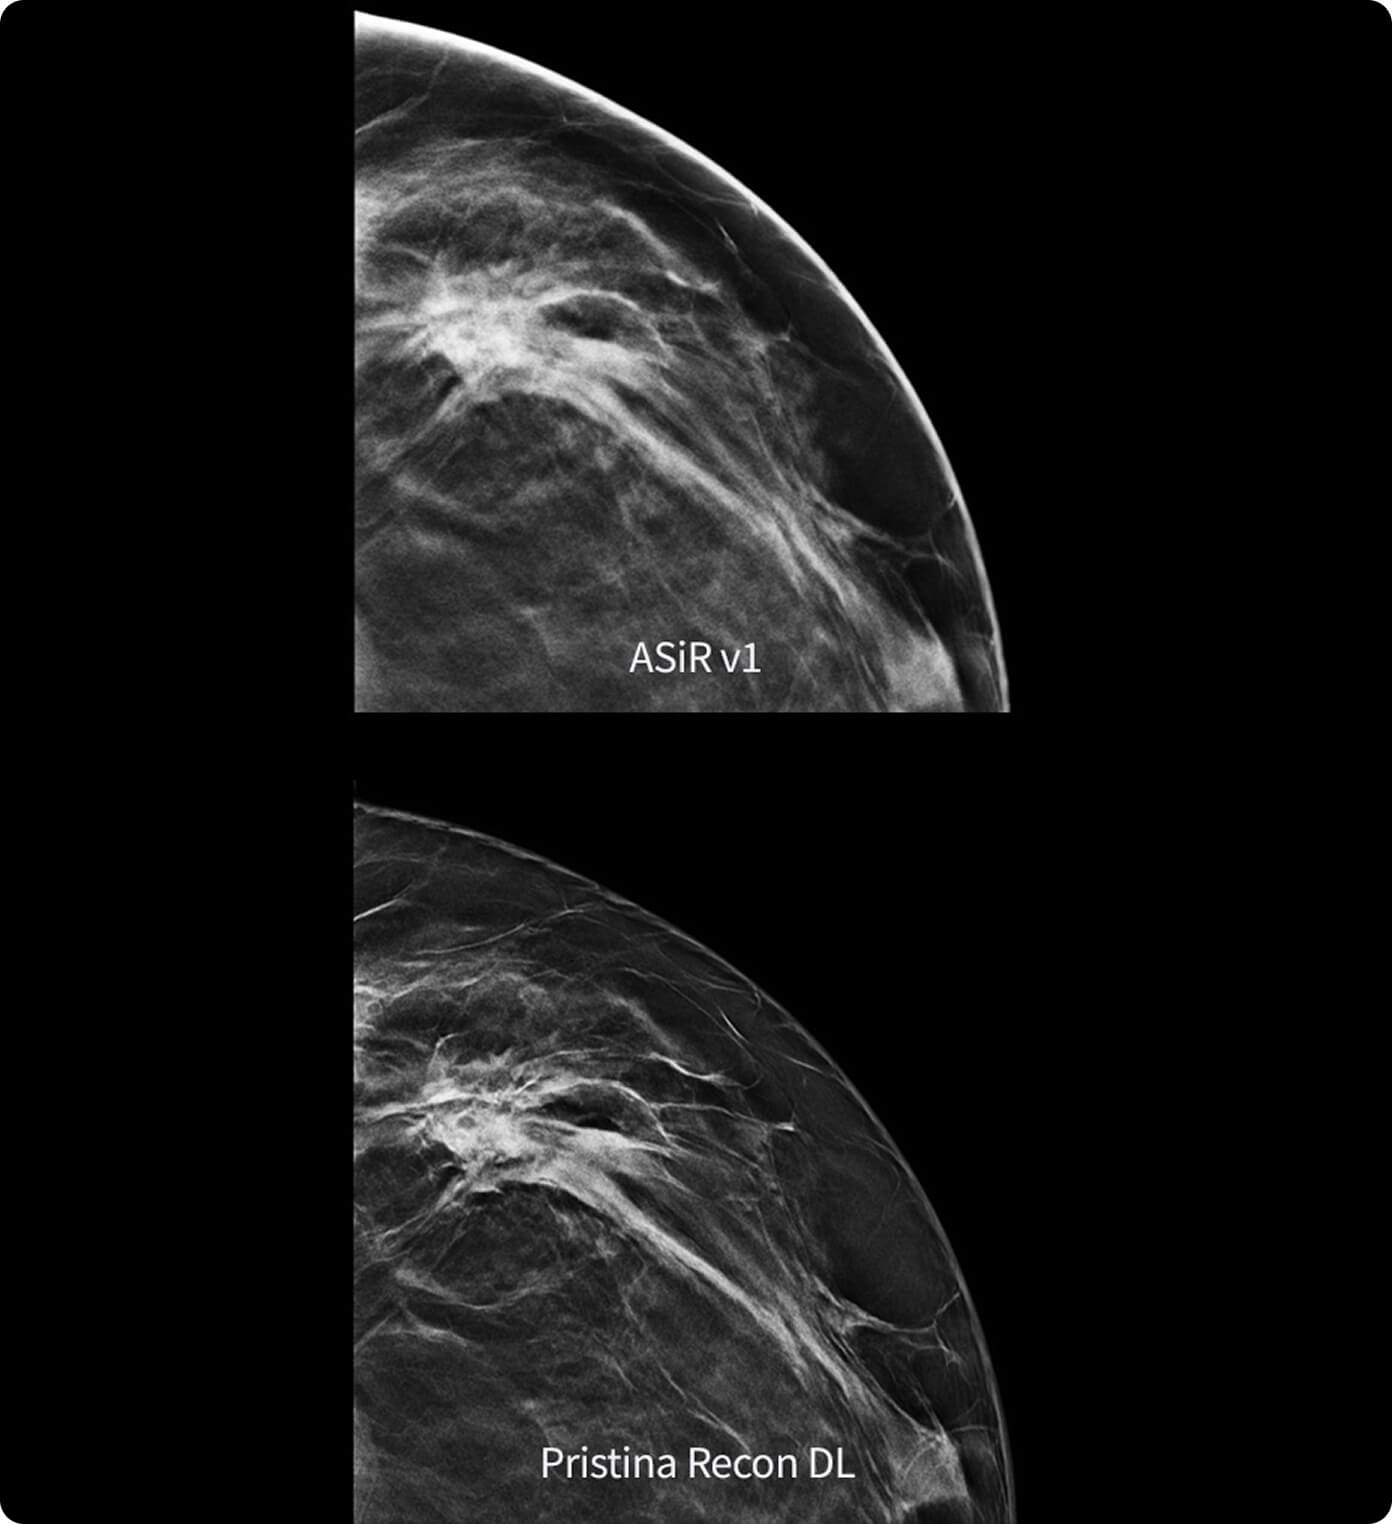

Scegli le innovazioni più recenti per migliorare la qualità delle immagini e ridurre la dose e gli artefatti. Oltre alle applicazioni Ricostruzione e IQ, il pacchetto base fornisce anche il software di sistema TC più recente e consente all'hardware² e alle soluzioni di automatizzare la selezione del protocollo TC.